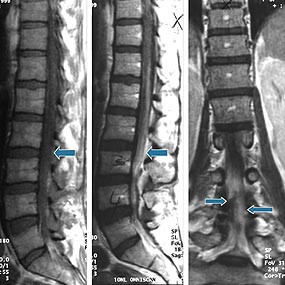

Et annet meget alvorlig problem illustreres av sykehistorien til pasienten 5, som utviklet epiduralabscess. Pasienten fikk flere akutte, kliniske symptomer og tegn på epiduralabscess (dag 43) i form av nevrologiske utfall med blæreparese, økende smerter i korsryggen samt høy feber, stigende CRP- og LPK-verdier. Det tok allikevel 15 dager fra mistanke om en epidural prosess ble fattet til pasienten ble operert. Dette er veldig lang tid når vi vet at en rask diagnose og kirurgisk dekompresjon er kritisk både av hensyn til overlevelse og alvorlig nevrologisk sekvele (8, 22). Det ble tatt tre serier med MR-bilder av columna med og uten kontrast som ble tolket som negative med henblikk på en ekspansiv prosess (fig 1). Gransker man litteratur vedrørende utseende av abscess på MR, viser det seg at noen fremstår som en ekspansiv prosess med kontrast oppladning svarende til granulasjonsvev. Andre derimot fremstår som diffus prosess som kan involvere mange spinale segmenter eller til og med hele spinalkanalen og er vanskelig å tyde (23 – 25). Mekanisk kompresjon av medulla er ofte ikke synlig, verken radiologisk eller ved autopsi. Derfor ble det foreslått at vaskular affeksjon (sekundær til infeksjon) i form av venekompresjon, trombose og tromboflebitt av vener i epiduralrom og medulla spinalis kan lede til nevrologiske symptomer (15).

Epiduralrom består hovedsakelig av fettvev og nettverk av vener, som krysses av nerverøtter. Dette byr på liten motstand mht. spredning av infeksjon. Derfor kan epidurale abscesser spre seg over mange segmenter. I tillegg kan de bestå av mye puss og lite granulasjonsvev, og grensen mot normalt vev blir ikke demarkert med MR-kontrast (fig 1). Derfor ble det foreslått at myelografi med CT kan være bedre ved diagnostikk av diffuse abscesser enn MR (23 – 25).